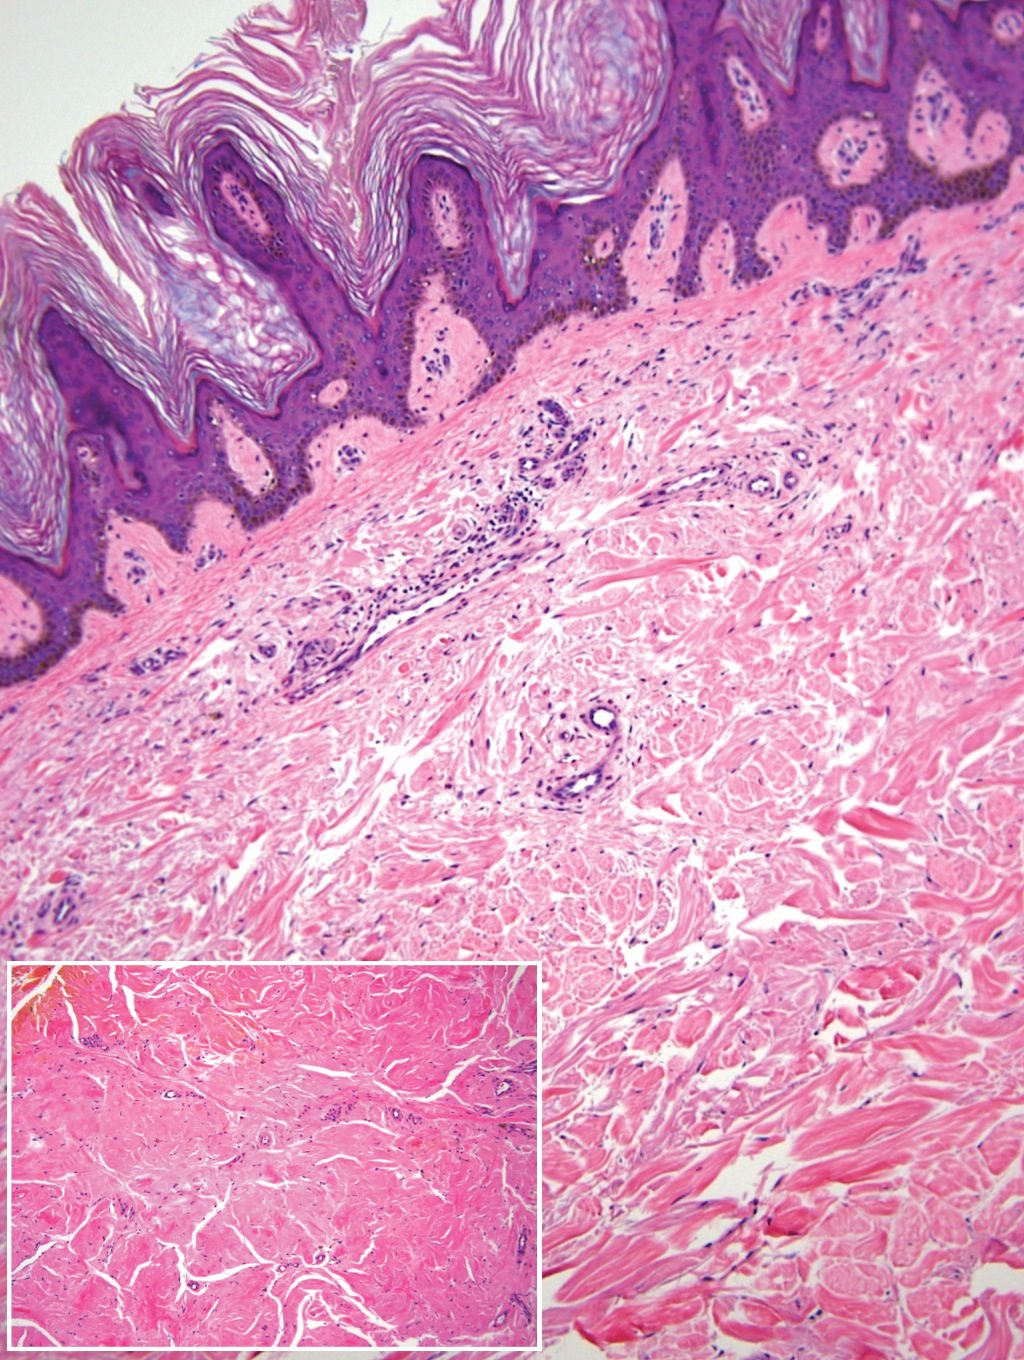

Remarkable laboratory data included a fasting glucose level of 207 mg/dL (reference range, 70–110 mg/dL) and a glycohemoglobin of 8.8% (reference range, <5.7%). Serum protein electrophoresis and immunofixation were normal. Histopathology of the lesions demonstrated diffuse deposition of pink amorphous material associated with prominent papillomatosis, hyperkeratosis, and acanthosis (Figure 2). Congo red staining was positive with green birefringence under polarized light, indicative of amyloid deposits (Figure 3). Liquid chromatography–tandem mass spectrometry of the specimens was consistent with deposition of AIns amyloidosis.

A majority of cases of iatrogenic amyloid have been described as single, firm, subcutaneous masses at an injection site that commonly are misdiagnosed as lipomas or lipohypertrophy.7-11 To our knowledge, none of the reported cases resembled the multiple, discrete, exophytic nodules seen in our patients.3,4 The surrounding hyperkeratosis noted in patient 1 is another uncommon feature of AIns amyloidosis (Figures 1 and 2). Only 3 AIns amyloidosis cases described lesions with acanthosis nigricans–like changes, only 1 of which provided a clinical image.6,7,12The mechanism for the acanthosis nigricans–like changes may have been due to the high levels of insulin at the injection site. It has been suggested that the activation of insulinlike growth factor receptor by insulin leads to the proliferation of keratinocytes and fibroblasts.6 Histologic examination of AIns amyloidosis lesions generally demonstrates deposition of homogenous eosinophilic material consistent with amyloid, as well as positive Congo red staining with green birefringence by polarization. Immunohistologic staining with insulin antibody with or without proteomic analysis of the amyloid deposits can confirm the diagnosis. In both of our patients’ specimens, liquid chromatography–tandem mass spectrometry was performed for proteomic analysis, and results were consistent with AIns amyloidosis.